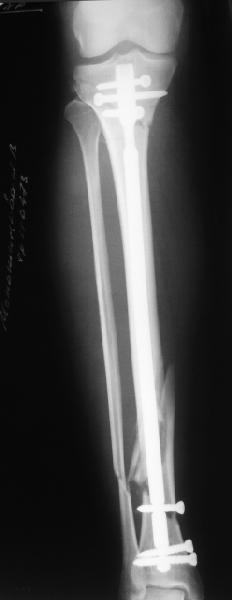

Сделали все-таки стержнем. На всякий случай просверлил дополнительное проксимальное отверстие, так что получилось три 45-градусных винта.

В дистракторе провеи спиц поболше в прокисмальном отделе, чтобы не разобщить фрагменты при сгибании колена. Комментарии и критика приветствуются.

We proceeded with nailing using a small wire distractor, with few wires at the proximal end to prevent displacement with forced knee flexion. Images attached. Comments and critics are welcome.

It is often a problem nailing upper tibial fractures. There is a tendency to apex anterior angulation as well as valgus alignment. Your entry point on the AP view seems to have been kept the same. How did you manage to maintain alignment? Any intra-operative pictures of your technique?

The lateral view shows your entry point to be quite posterior and I think this is recommended to avoid anterior angulation. Were you concerned about intra-articular penetration?

Overall an excellent post-op x-ray. Well done.

As i mentioned a small wire distractor was used. In common upper fractures it is enough to insert 2 frontal wires to the proximal fragment - one in the upper posterior aspect of the tibia and the second anteriorly and a bit more distally. The technique allows to avoid such known tricks like more lateral entry point, semi-extended knee, extended approach, using of bone clamps, plating with monocortical screws etc.

In this particlar case 4 frontal wires were inserted in anterior and posterior aspects at both sides of proximal fracture, and fixed to a single half ring with some bend to provide compression with wire tension. Image attached.

You are absolutely right, and the entry point could be more anterior without the risk of angulation. This a bit posterior placement was caused by the proximal anterior wire. No obvious problem with the knee though.